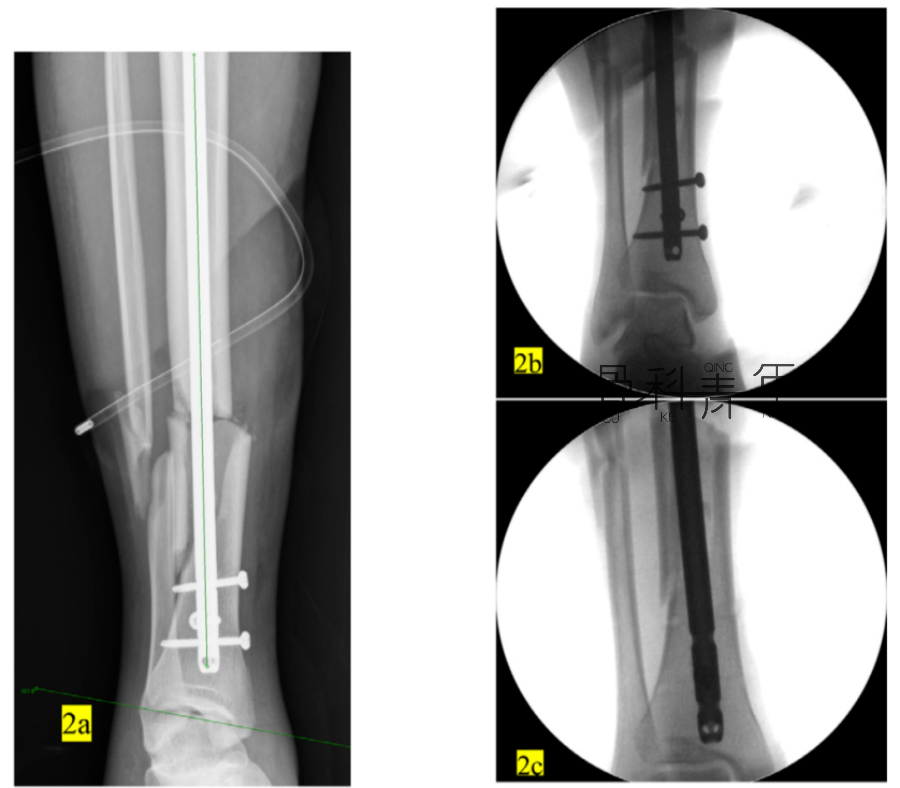

病例示例2:

2a-2c:胫腓骨远端骨折,髓内钉固定,主钉插入及远端锁钉锁定后,可见骨折对线不良,存在移位。

2d-2f:依同法在移位平面拧入螺钉纠正移位,恢复对线后置入阻挡钉维持复位。